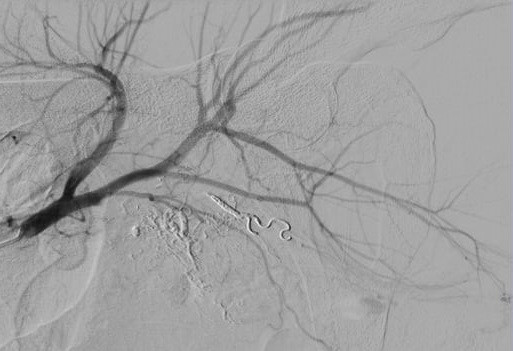

Sau nút mạch quanh động mạch trực tràng. (Ảnh: BVCC)

Tuy nhiên với bệnh nhân này, chúng tôi cần tìm thêm các nhánh chảy máu quanh trực tràng, gồm sáu nhánh mạch hai bên: động mạch trực tràng trên, động mạch trực tràng giữa và động mạch trực tràng dưới. Sau khi xác định được nhánh chảy máu, chúng tôi phải lựa chọn vật liệu gây tắc mạch cũng như vị trí can thiệp để không bị hoại tử trực tràng”, BS Giang cho hay.